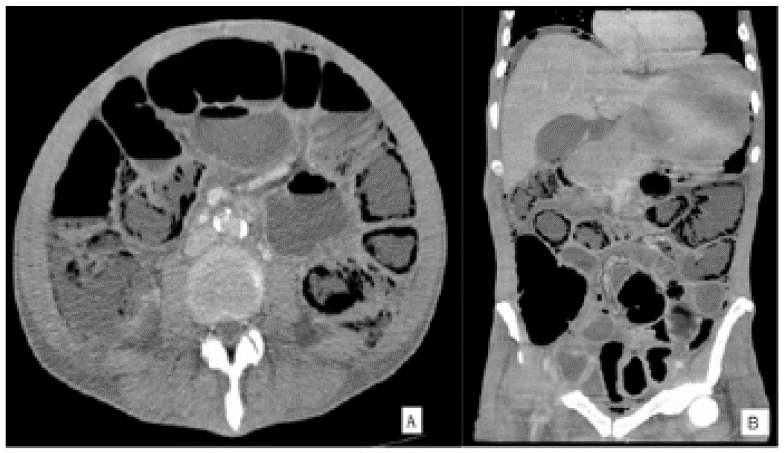

Se trataba de una mujer de 66 años sin antecedentes personales relevantes y quien consultó por un dolor abdominal difuso sin otros síntomas asociados. Al examen físico no se encontraron signos de irritación peritoneal. Se solicitó tomografía de abdomen contrastado en la que se identificaron múltiples imágenes hipodensas con unidades hounsfield (UH) promedio de -967, con morfología circular y lineal comprometiendo la pared del colon transverso (figura 2). No se observó aire en la vena porta, neumoperitoneo ni otras complicaciones. Se le realizó colonoscopia la cual no encontró anormalidades. La paciente fue manejada de forma expectante con mejoría de su cuadro clínico, por lo que se realizó el diagnóstico de neumatosis quística.